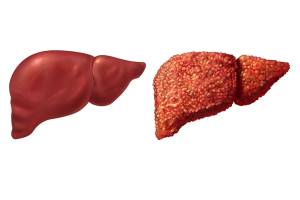

Асцит – одно из значимых осложнений цирроза, возникает у 50% пациентов за 10-летний период от постановки диагноза. Развитие асцита считают важным неблагоприятным прогностическим признаком прогрессии цирроза, так как он связан с 50% смертностью в течение..